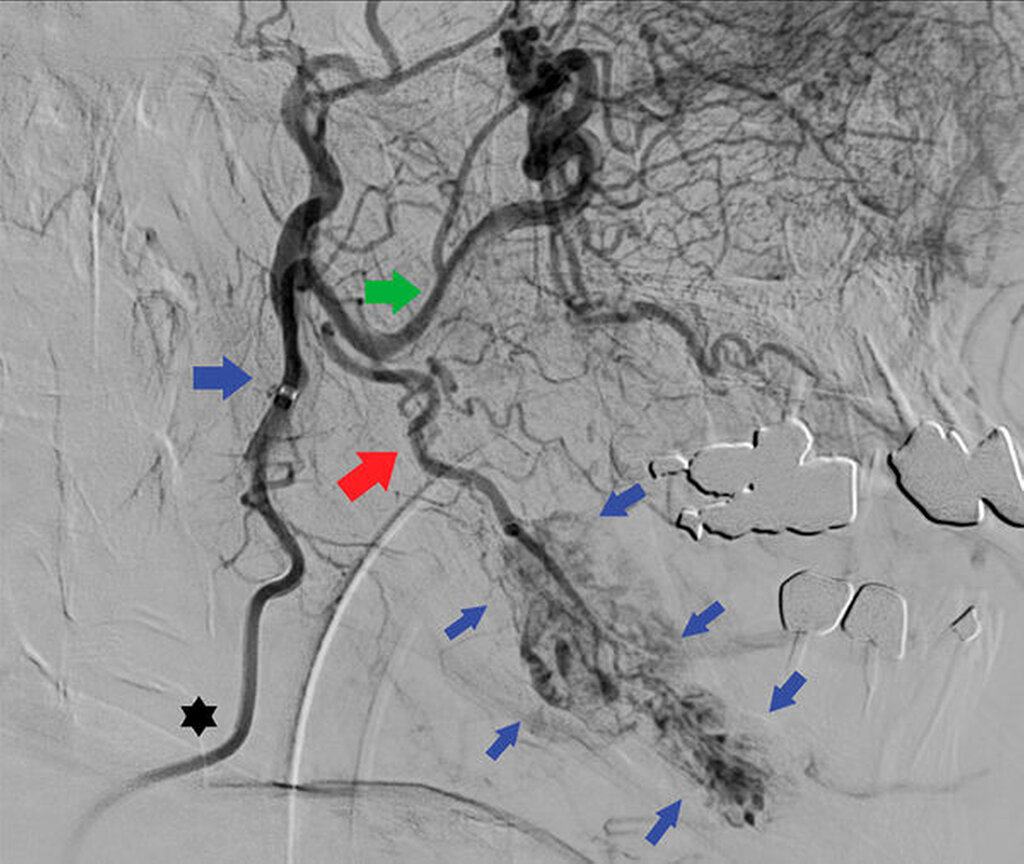

Als weitere diagnostische Abklärung wird anschließend eine transfemorale Katheterangiografie der kraniozephalen Gefäße in intraarterieller, digitaler Subtraktionsangiografie durchgeführt. Es wird eine osteodestruktive Formation mit kräftiger, blush-artiger, spätarterieller Kontrastmittelanreicherung mit teils dilatierten Venen und venösem Abfluss beschrieben. Weiterhin kann die linke Arteria facialis als arterieller Hauptfeeder identifiziert sowie ein pathologischer Zufluss von kontralateral ausgeschlossen werden (Abbildung 3).